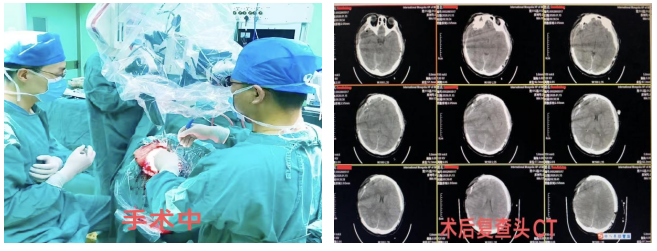

患者生命体征极不平稳,危在旦夕,神经外科王凤副主任医师立即向段英俊主任汇报了患者病情,决定由王凤副主任医师、张泽峰副主任医师、蔡沐宇医师成立手术抢救小组,并迅速联系麻醉手术中心、重症医学科、输血科,请示医院开通绿色通道紧急由CT检查室推病房床直接进入手术室。

手术开始前查体患者双侧瞳孔均已散大,对光反射消失,经与患者家属沟通后行右侧额颞顶部硬膜下血肿清除去骨瓣减压术+颅内压探头置入术+左侧颞顶部硬脑膜外血肿清除术。

术中采用多点硬脑膜开窗法(MDF)清除右侧额颞顶部大量硬膜下血肿,右侧额颞叶可见广泛脑挫裂伤,显微镜下予以清除失活的脑组织,彻底止血后置入颅内压探头进行颅压监测;翻转头部行左侧颞顶部硬膜外血肿清除,术中见左侧颞顶骨粉碎性骨折,骨折线向颅底延伸,硬膜外血肿量约40ml予以清除,并彻底止血。术中多次血压波动,麻醉科包木仁主任医师给予精准调控,手术顺利完成,术后患者转至重症医学科继续治疗。

手术的顺利实施只是成功的第一步,因患者病情极其危重,术后严重的脑水肿、肺部感染、凝血功能障碍、电解质紊乱等术后并发症的出现仍是阻碍患者顺利康复的多重难关。在重症医学科王帅副主任医师精心医治和护士团队的精心护理下患者病情逐渐趋于稳定,术后10天患者意识转清,目前已转入普通病房进行后续治疗。